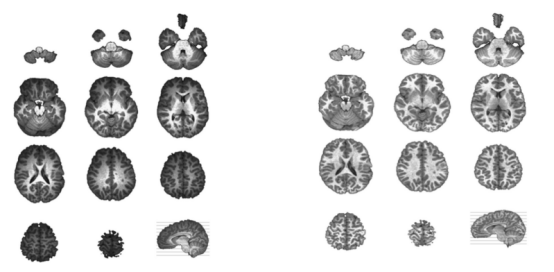

EEG源成像的头部模型是基于MRI的,为了正确提取与头部形状、颅骨厚度和灰质体积等有关的信息,需要进行以下几个步骤:重新采样和重新定位、颅骨剥离、偏场校正,以及灰质和白质分离。下面介绍如何使用Cartool实现这些步骤。

在分析过程中,我们需要得到一个标准化的个体头部模型。因此,我们的下一步是剥离颅骨以分离颅骨、脑脊液和大脑(图6)。

MRI处理的最后一步便是白质与灰质分离。这是因为EEG源定位通常将源空间限制在包含突触的灰质中。Cartool能够使用混合高斯函数来估计灰质、白质和脑脊液的整体强度分布,从而提取gray mask(图8)。